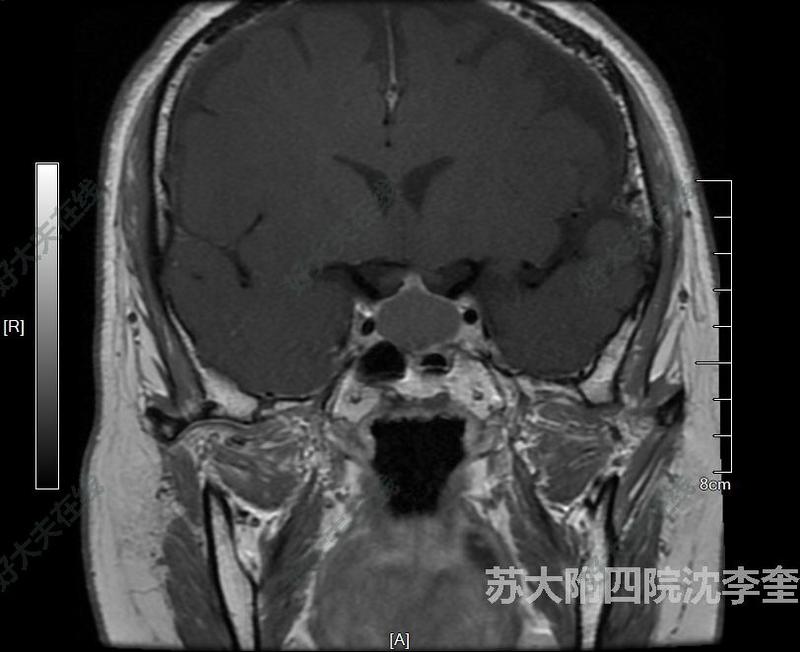

治療前患者垂體瘤,一致無明顯癥狀,近期出現(xiàn)視力改變,視力改變是一個非常有用的信息,很多患者不太重視,一旦出現(xiàn)視力影響是盡快手術(shù)的一個明確信息,應(yīng)該引起重視,早期視力受損是可逆的,晚期視力受損往往不可恢復(fù)。因此患者及時進行了手術(shù)治療治療中患者腫瘤不是特別大,因此采用了經(jīng)鼻黏膜下入路,黏膜下入路可以很好的保護患者的嗅覺黏膜,避免術(shù)后嗅覺障礙。這是目前大多數(shù)經(jīng)鼻手術(shù)無法平衡的一個難點和痛點。手術(shù)中采用了假包膜分離,徹底切除腫瘤,并且鞍底進行了縫合,有效防止術(shù)后腦脊液漏。治療后治療后即刻患者術(shù)后鼻腔不需要任何填塞,鼻腔舒適性較以前手術(shù)案例大幅提高。術(shù)后鼻腔嗅覺很快恢復(fù)。術(shù)后復(fù)查核磁提示腫瘤徹底全切除,無腦脊液漏發(fā)生。

沈李奎醫(yī)生的科普號2024年11月25日121